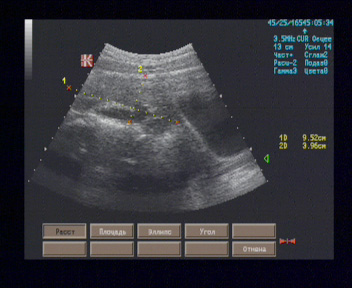

Правая почка визуализируется на уровне подвздошной кос ти справа, размерами 93 х 43 мм, форма типичная, почка ротирована, контуры волнистые, паренхима толщиной 18 - 22 мм, однородная, равномерно гипоэхогенная, кортико-медуллярная дифференцировка умеренно выражена, ЧЛС расширена до 12 мм, просвет свободен.

Левая почка лоцируется позади мочевого пузыря слева, ротирована, размерами 92 х 42 мм, форма типичная, контуры волнистые, паренхима толщиной 18 - 21 мм, однородная, равномерно гипоэхогенная, кортико-медуллярная дифференцировка умеренно выражена, ЧЛС расширена до 12 мм.

При сканировании стоя положение правой почки не меняется.

Эхографические признаки тазовой дистопии левой почки и пояснично-подвздошной дистопии правой почки.